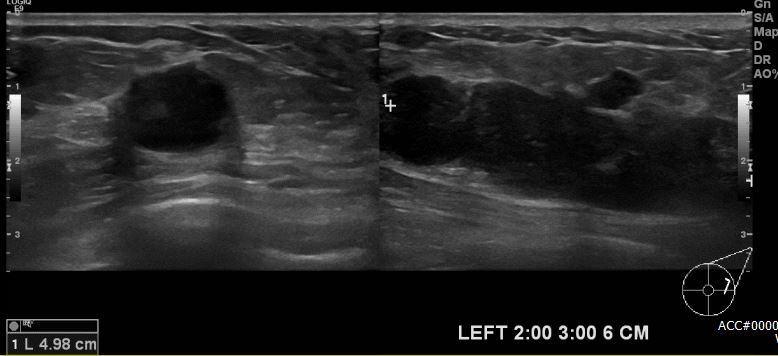

상기환자 좌측 유방에 만져지는 멍울로 내원하신 50대 여성분으로 좌측 2시에서 3시

방향에서 6cm 떨어진 거리에 만져지는 멍울 조직검사 시행하여 좌측 침윤성 유관암

진단되었습니다.